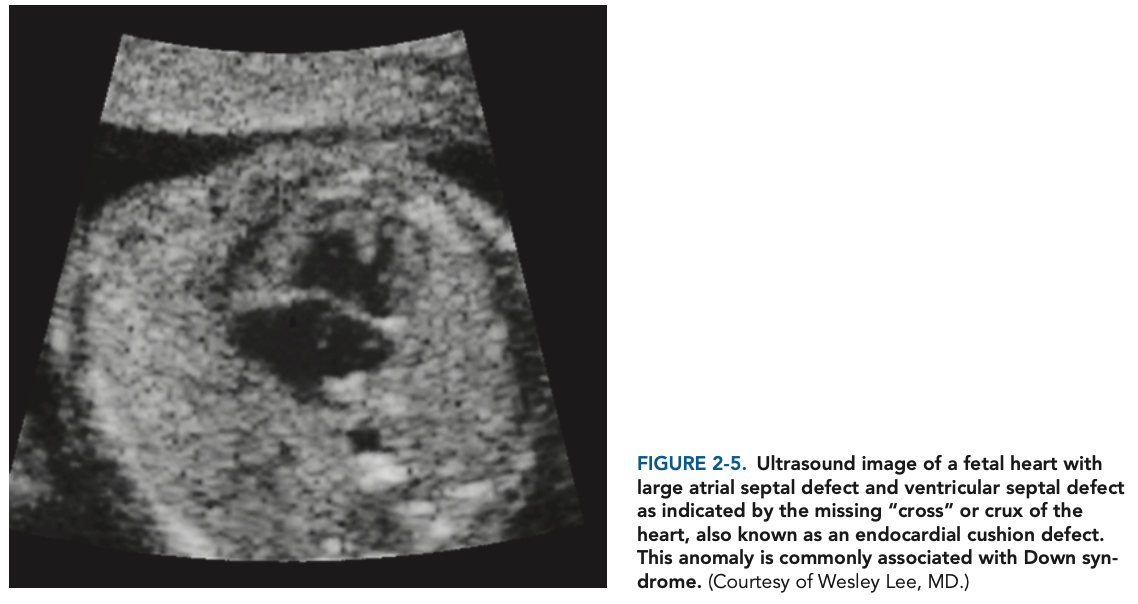

A single palmar crease; small, folded ears; a short neck; Brushfield spots (pale yellow spots on the iris); and a gap between the first and second toes. They also suffer from heart disease, most often cardiac cushion malformations (Figure 2-5), and may have ophthalmologic problems, gastrointestinal tract malformations, poor hearing, and mental retardation. Males with Down syndrome are almost always infertile.